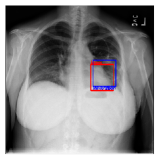

CXR8 [21] is one of the most commonly accessible radio-logical examination for many lung diseases. The data consists of 112,120 images collected by 30,805 patients. As shown in Table I, nine class labels of normal state and eight diseases including cancer are defined for classification. The data is divided into training set and test set, and the classification accuracy and ROC curve with several well-known deep network such as VGG16, GoogLeNet, and ResNet, are reported on the original paper [21]. In addition, 984 Bounding Boxes (B-Box) are provided for localization. Fig. 5 shows image examples of CXR8. The red rectangle in the image shows given B-Box.